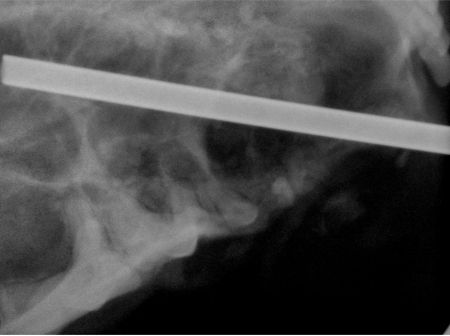

Neoplasia, particularly odontogenic tumors, must be considered. Infection is possible but unlikely because of the character of the mass and the lack of pain on palpation. The most likely cause is a dentigerous cyst associated with the right maxillary canine tooth. Although definitive diagnosis can only be made with histopathology, dental radiography is extremely valuable in determining the cause in these cases. Photo 2 shows the tooth displaced caudally and toward the midline within the relatively lucent right maxilla.

Photo 2: The canine tooth is displaced caudally and toward the midline within the relatively lucent right maxilla.

The tooth itself was forced caudally and toward the palatal midline residing within the maxillary sinus at its caudal extent. The suction wand can be seen radiographically at the caudal-most point of cyst expansion (Photo 5). The tip lies within suborbital bone.